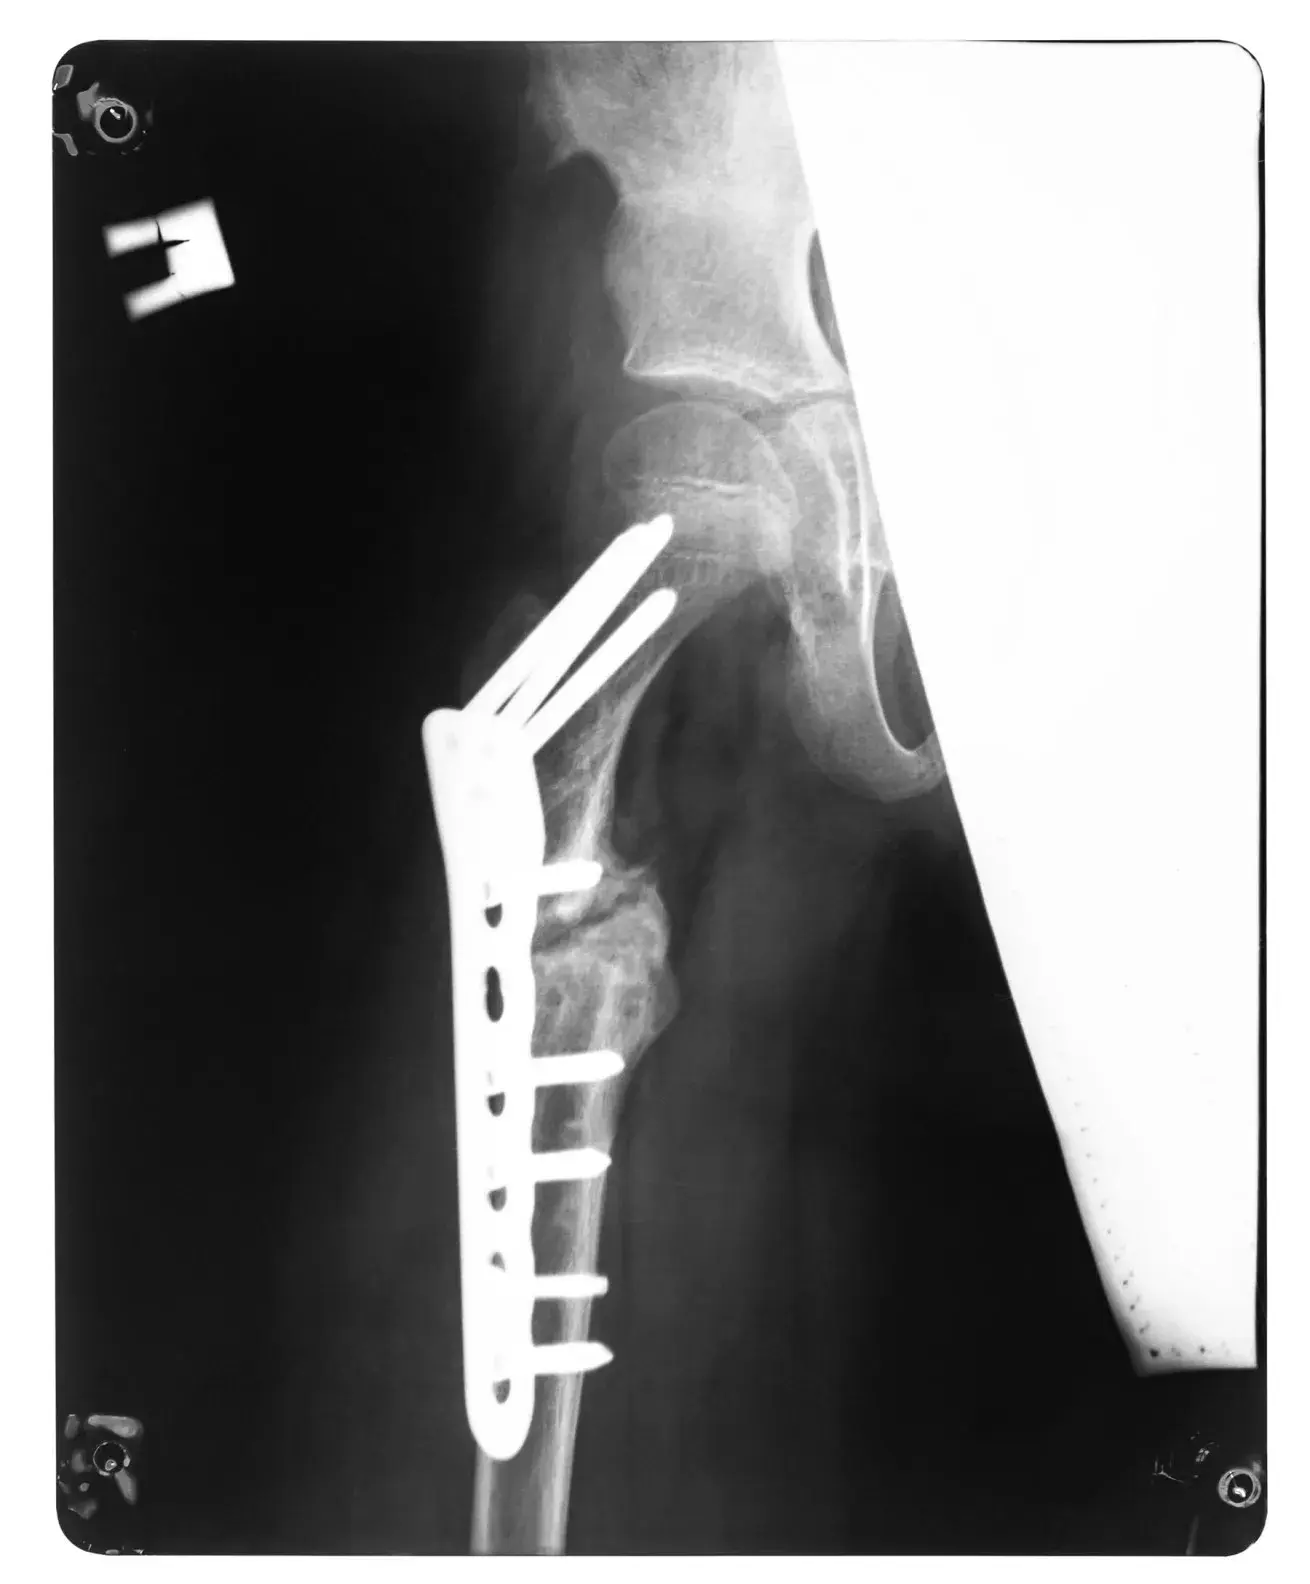

Femoral fractures are a common injury among active individuals, often resulting from high impact falls during running, cycling or skiing. These fractures typically require surgical intervention in the form of Open Reduction Internal Fixation (ORIF) to stabilise the bone and allow for proper healing.

Following surgery, rehabilitation is crucial for restoring function and facilitating a return to sport or daily activities. The recovery timeline varies based on the severity of the fracture, surgical fixation, and individual healing response.